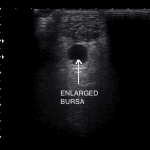

Performing an ultrasound of the foot indicted a large Retrocalcaneal bursa (Retrocalcaneal bursitis) and  Achilles Tendinopathy (click for more information)

Ultrasound image of ankle tendons showing thick Achilles and bursitis, highlighting orthopaedic assessment and treatment for ankle and foot conditions in Melbourne. ultrasound of enlarged bursa